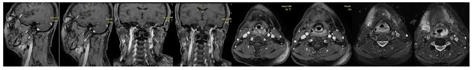

2周期疗效评价部分缓解,4周期疗效评价完全缓解。

外科会诊考虑手术难度大,需整形科协助,且患者不同意手术。于2021年5月至2021年8月行4周期吉西他滨+顺铂方案(GP方案)化疗联合特瑞普利单抗免疫治疗。

鼻咽癌是具有地区特异性和种族相关性的头颈部恶性肿瘤,亚洲和北非发病率较高。中国华南地区鼻咽癌高发。放疗是鼻咽癌的主要治疗方法。近20%的局部晚期鼻咽癌患者初次放疗后出现局部复发[4,5]。对于局部复发鼻咽癌,手术、化疗或再程放疗是主要治疗手段。研究认为初次放射治疗预后良好(如局部复发小、淋巴结负荷低、间隔时间长;>3年)的患者可能从再程调强放疗(60-70Gy)中获益[6,7,8]。本病例经过初次放化疗后40个月左右出现鼻咽局部复发,给予再程放疗。遗憾的是,再程放疗后不到2年即再次出现颌下进展。由于肿瘤累及部位邻近既往放疗野或位于低剂量区,距离首次治疗5年左右,需要鉴别鼻咽癌治疗后复发进展或是放疗诱发第二原发恶性肿瘤(radiation-induce second malignancy neoplasm, RISMN)。经病理学检测提示鼻咽癌治疗后进展,与首次治疗病理类型相同,根据RISMN目前诊断标准[9],考虑鼻咽癌复发治疗后再次复发。与首次鼻咽部复发不同的是,二次复发位于颌下及颈部区域。对于局部或区域复发性鼻咽癌,可推荐手术或放疗。挽救性手术仅适用于可切除的复发性病灶[10]。本病例病变范围偏大,患者为再程放疗后复发,涉及颌面部手术重建、手术难度大、严重并发症等问题,以及患者对手术治疗的意愿,不考虑手术治疗。再程放疗后复发鼻咽癌,复发时间、放疗剂量及其预期疗效、潜在严重并发症提示该患者不宜行放疗。因此,局部治疗(外科,放疗)难以实施。化疗是不可手术切除或不可再次放疗患者的选择[8],吉西他滨联合顺铂(GP方案)是复发转移性鼻咽癌的标准一线治疗方案[11,12]。由于患者是二次复发,推荐使患者有更大获益的治疗方案。患者EB病毒阳性,这类患者鼻咽癌淋巴细胞浸润密集,50%~80%的患者PD-L1表达阳性,基础和临床研究均提示复发转移性鼻咽癌患者可从PD-1/PD-L1治疗中获益[13,14,15,16,17,18,19,20,21]。特瑞普利单抗是一种人源化IgG4 PD-1抗体,在多中心II期研究(POLARIS-02)中[15]分析了可评估的190例复发转移性鼻咽癌患者,特瑞普利单抗治疗客观缓解率(overall response rate, ORR)为20.5%,疾病控制率(disease control rates, DCR)为40%,中位反应时间为1.8个月,缓解持续时间(duration of response,DOR)12.8个月,中位生存期(median survival time)17.4个月。14.2%患者出现3-5级免疫相关副反应,治疗相关副反应主要包括甲状腺机能减退(2.6%)、肝功能异常(1.6%)等。研究还显示治疗28天后EBV-DNA下降大于50%的患者ORR高于EBV-DNA下降低于50%的患者[15],这提示特瑞普利单抗可作为复发转移性鼻咽癌的二线治疗方案。GP方案是复发转移性鼻咽癌的标准一线治疗方案,JUPITER-02研究比较了特瑞普利单抗与安慰剂联合GP方案一线治疗复发转移性鼻咽癌的疗效,中期结果提示特瑞普利单抗组和安慰剂组中位无进展生存期(progression free survival,,PFS)分别为11.7个月和8个月;1年无进展生存率分别为49%和28%;ORR分别为77.4%和66.4%(P=0.033);中位DOR为10.0个月和5.7个月。两组毒副反应相似,这提示特瑞普利单抗联合GP方案有望成为复发转移性鼻咽癌患者新的治疗方案[22]。考虑到本例患者为治疗后第二次复发,其首次复发仅接受调强放疗,且该患者再次复发治疗时上述成果尚未发表,参考复发转移性鼻咽癌治疗方案,给予GP方案联合特瑞普利单抗治疗,患者治疗后28天内EBV-DNA降至正常,2周期化疗部分缓解(partial remission,PR),4周期化疗后达完全缓解(complete remission,CR),未出现明显毒副反应。患者后续治疗是维持治疗或观察,尚不明确,其长期预后需进一步观察。